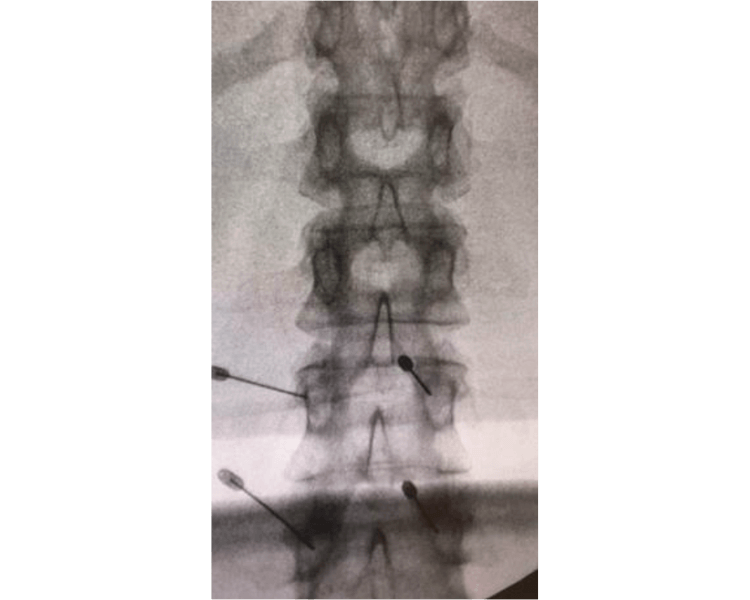

O Procedimento: Precisão Guiada por Imagem

O grande diferencial da infiltração na coluna é a precisão. O procedimento é sempre guiado por métodos de imagem. Os mais comuns são a fluoroscopia (um tipo de raio-X em tempo real), a tomografia computadorizada e o ultrassom.

Essa tecnologia permite que o médico visualize a coluna vertebral em detalhes. Assim, a agulha pode ser inserida com extrema exatidão no local desejado. Isso garante que o medicamento seja entregue diretamente na fonte da dor, maximizando a eficácia.

Durante o procedimento, um contraste pode ser injetado. Isso ajuda a confirmar a posição correta da agulha e a distribuição do medicamento. O médico acompanha todo o processo em um monitor, assegurando a segurança e a precisão